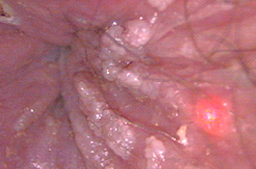

Pene con lesiones por vph planas y acuminadas.